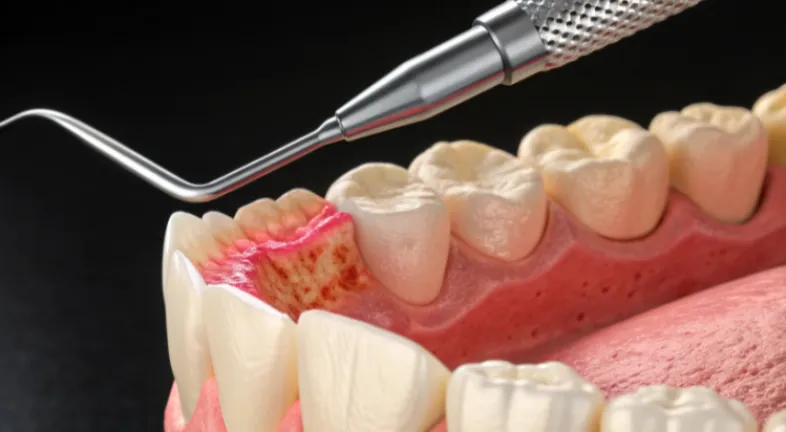

Gingivitis Treatment: How to Reverse Early Gum DiseaseGingivitis tends to creep up quietly, usually after a stretch of rushed brushing or nights where flossing just slips your mind. The first sign is often bleeding when you spit toothpaste into the sink. That moment makes people Google how to cure gingivitis, which is honestly the right instinct. Early gum inflammation happens because plaque irritates the tissue around the teeth. If you respond quickly, it is fully reversible. Most cases improve quickly with proper cleaning, hydration and small tweaks in daily habits. The key is not ignoring those early red or puffy gum signals.